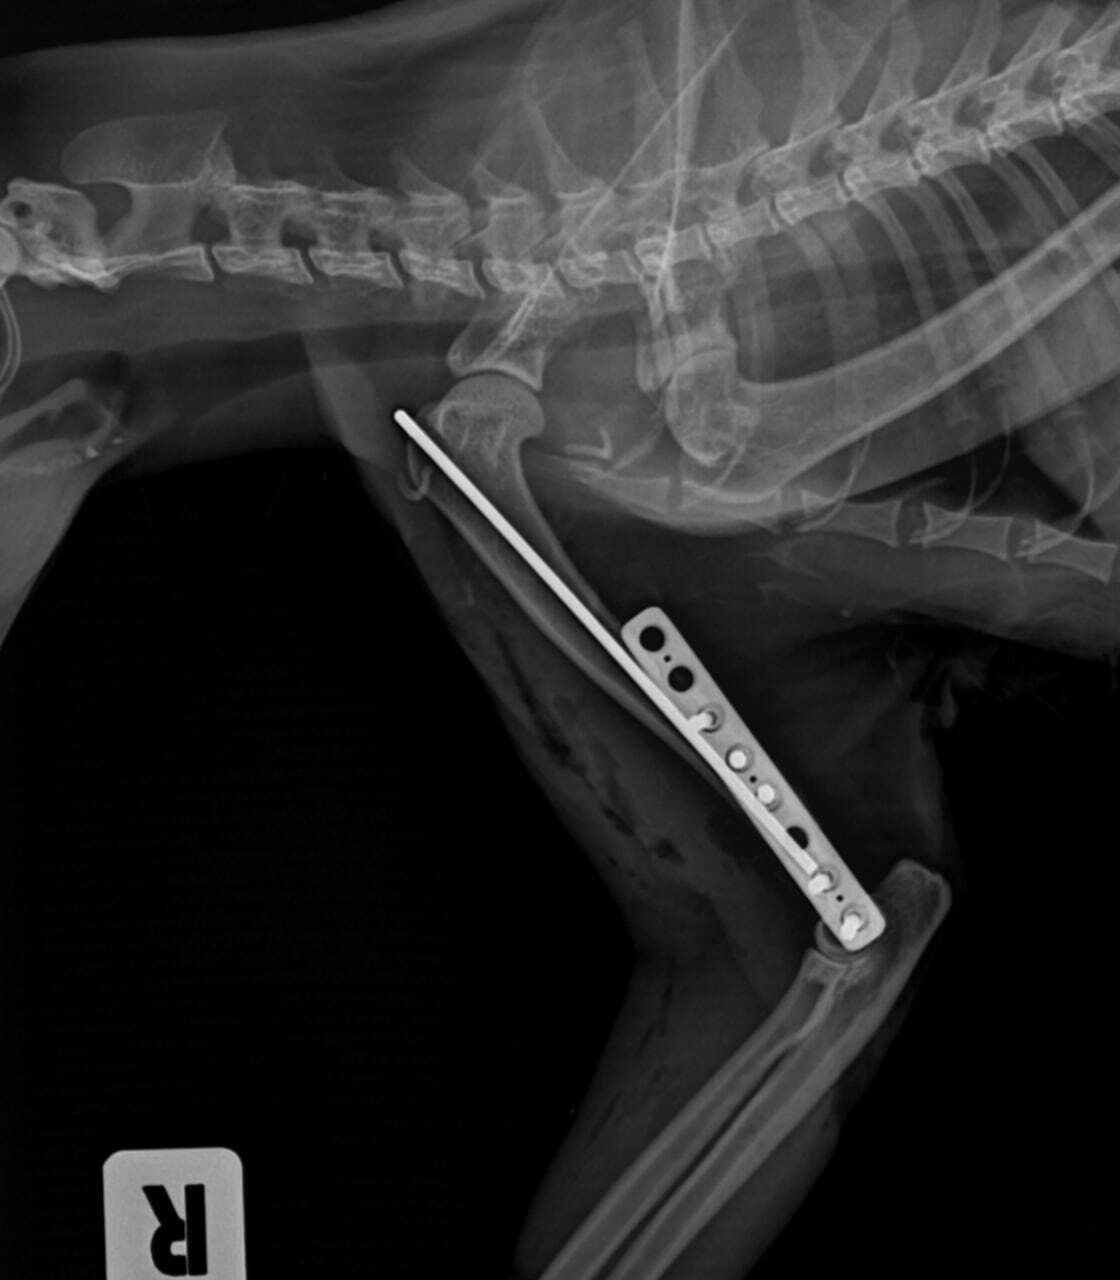

Сейчас она у меня дома в переписке. Похоже, вывихнута лапа, сильный стресс. Пока ничего не пьет, не ест.

Завтра поедем в ветеренарку....